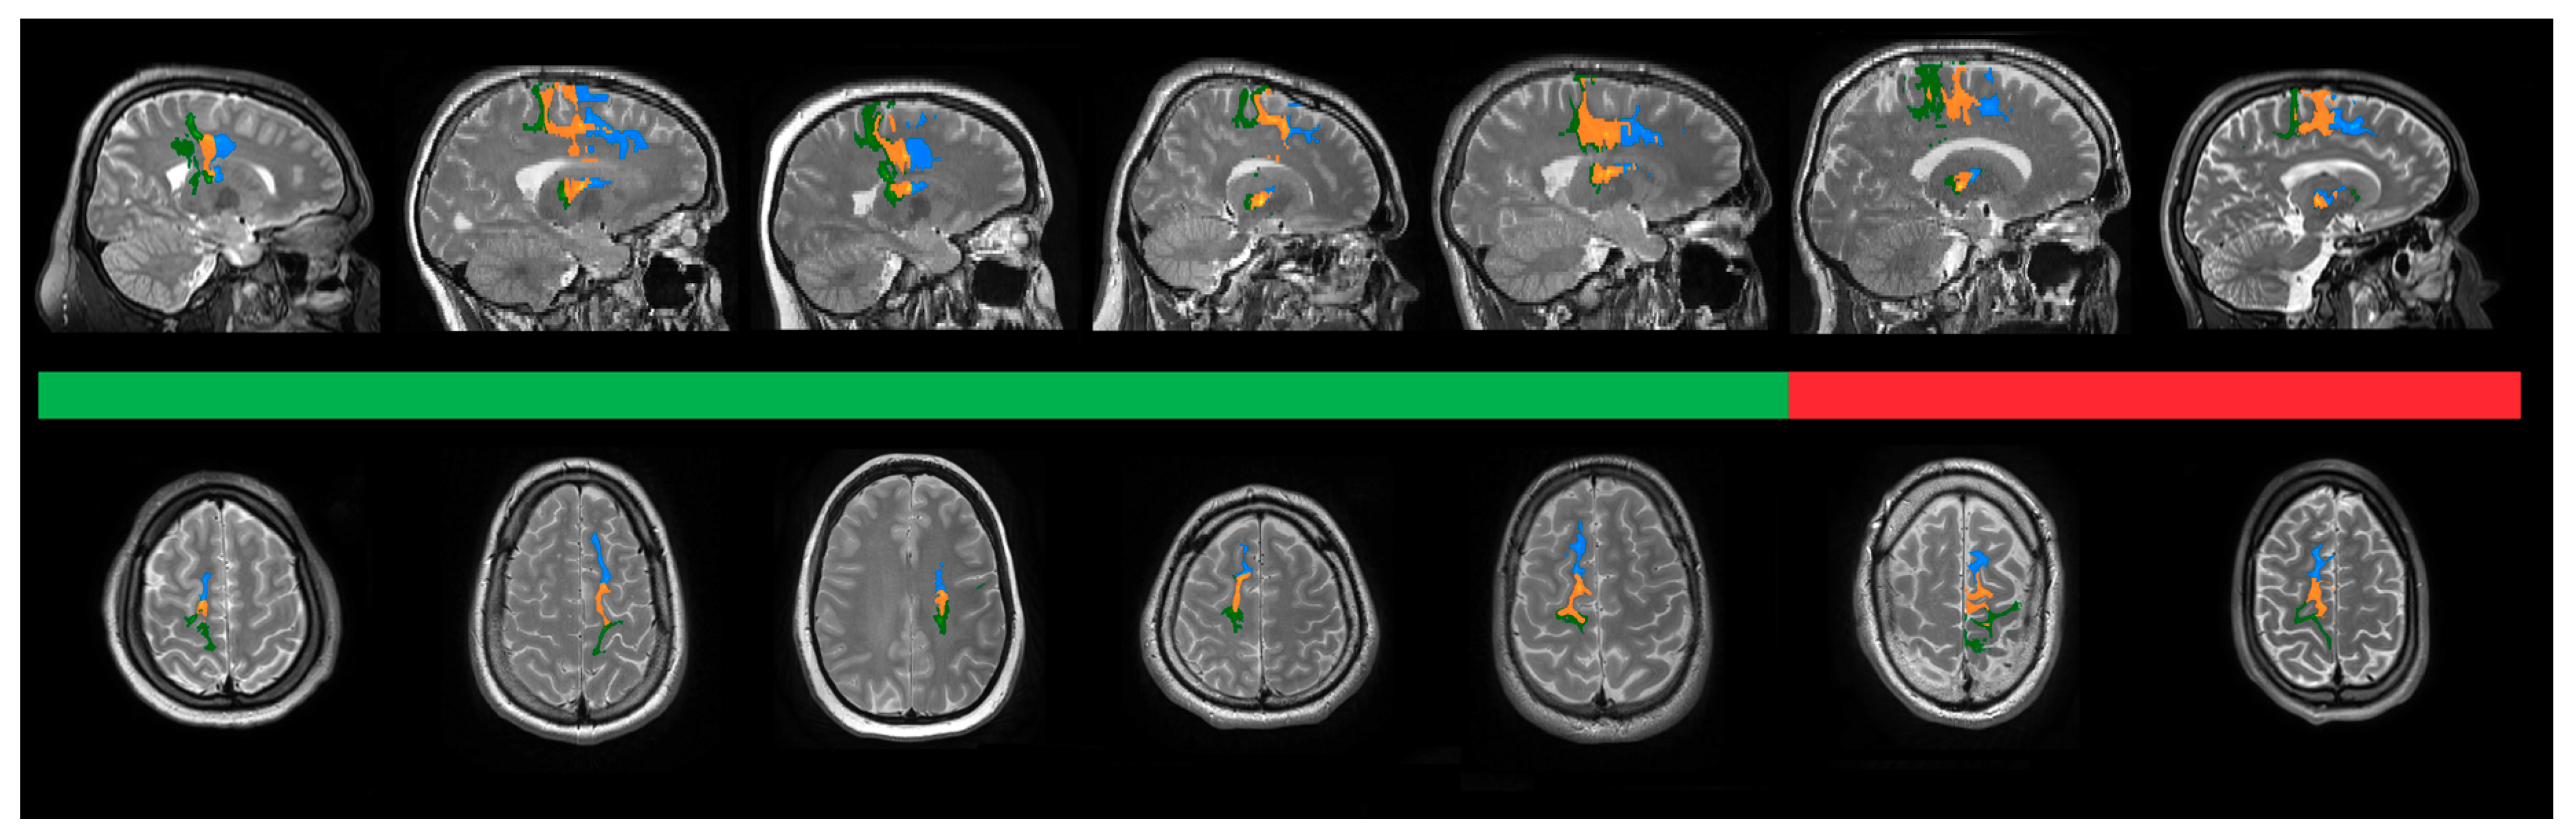

3.2.2. Parcellation of Seed Regions

3.2.3. Density of Fibers in the Motor Cortex